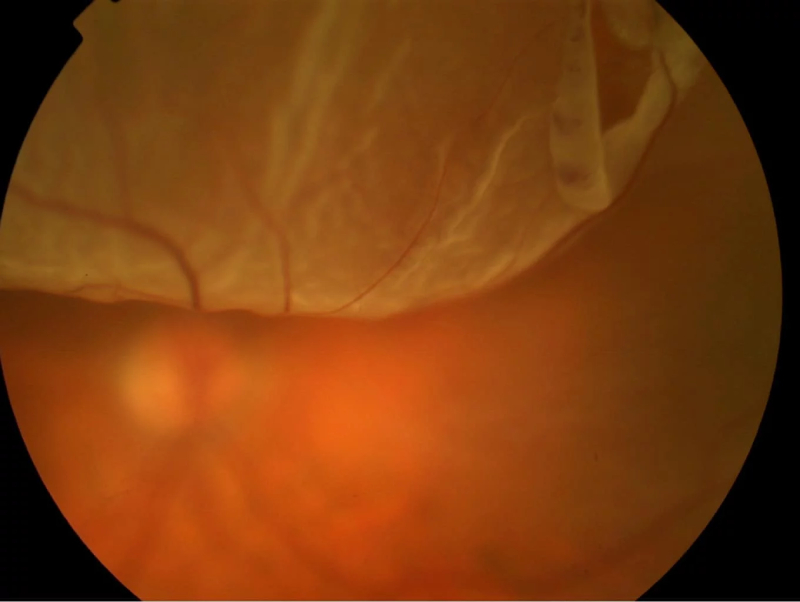

Cận 8 độ nhìn được bao xa, cận 8 độ có nguy hiểm không? Cận thị nặng là một trong những nguyên nhân chính gây suy giảm thị lực, nếu không được kiểm soát có thể dẫn đến nhiều biến chứng nguy hiểm như:

Ngoài ra thoái hóa điểm vàng, lỗ hoàng điểm, nhược thị, lác mắt,… cũng là những biến chứng nguy hiểm khác của cận thị nặng.